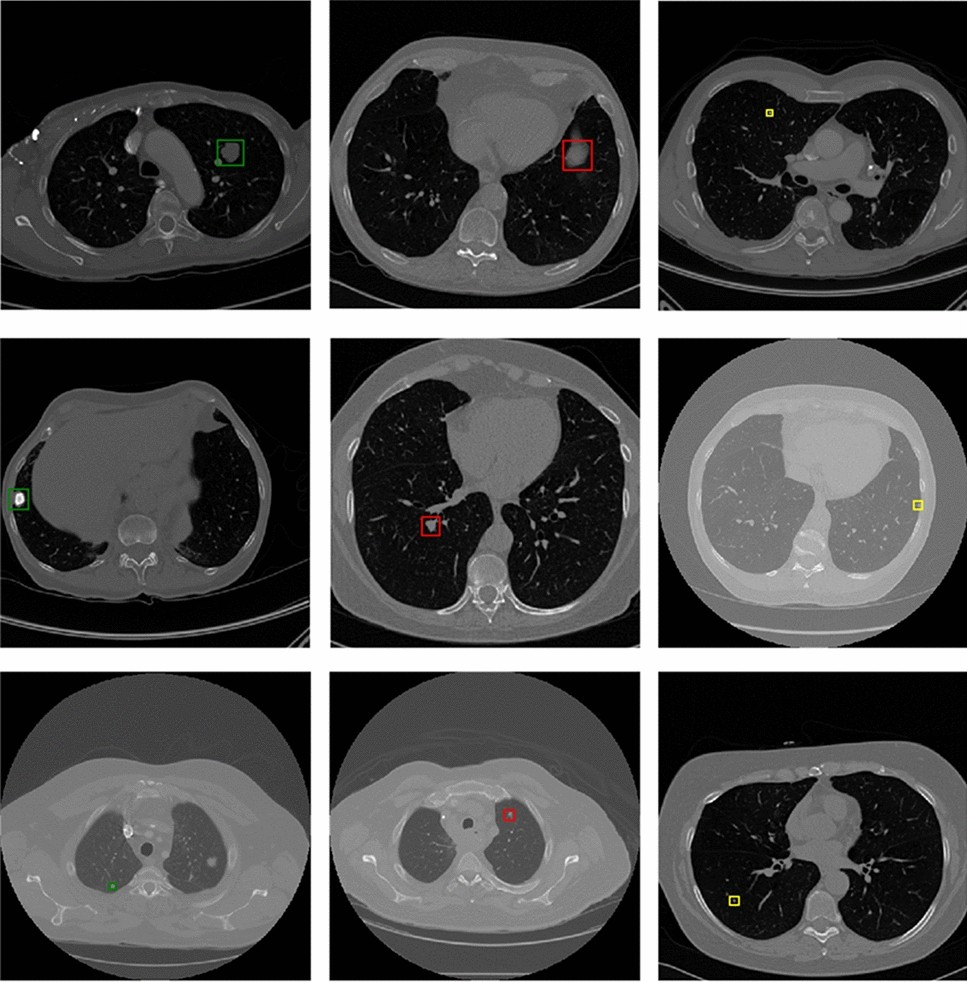

Detection results of true positive nodules, false positive nodules and false negative nodules.